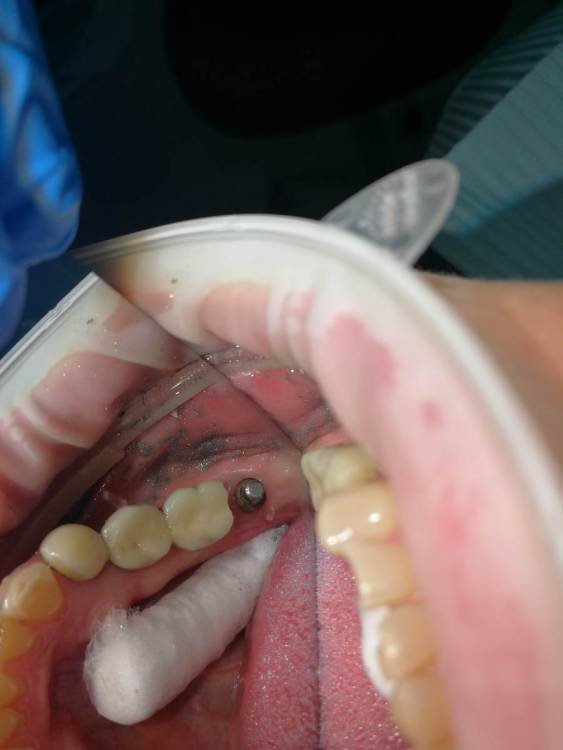

Turalyon Опубликовано 24 декабря, 2021 Поделиться Опубликовано 24 декабря, 2021 Приветствую, коллеги. У пациентки лет 10 назад установлены предположительно импланты Straumann, планируется замена коронок. Под старой коронкой вот такой мультиюнит, не знаю чем открутить. В каталоге подходящих ключей не нашел. 1) каким ключом можно попробовать открутить? диаметр около 3 мм 2)Что, если не откручивая снять оттиск с уже установленных мультиюнитов для изготовления новых коронок? Ссылка на комментарий

kramer Опубликовано 24 декабря, 2021 Поделиться Опубликовано 24 декабря, 2021 Это не мультиюнит, а монолитный абатмент. Откручивается специальным ключом. Или снимать оттиск с уровня абатмента 1 Ссылка на комментарий

Turalyon Опубликовано 2 января, 2022 Автор Поделиться Опубликовано 2 января, 2022 Спасибо за советы, связался с представителем штрауманн, ключ для подобных абатментов у них имеется. Сами абатменты в подобном исполнении сняты с производства, хотя раньше их широко применяли. Ссылка на комментарий